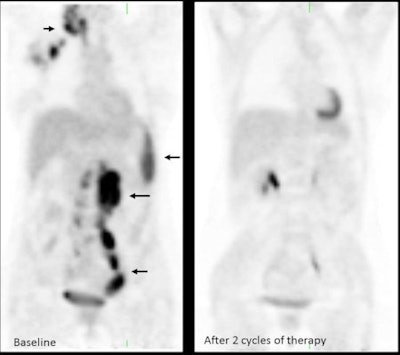

FDG-PET can accurately identify residual viable disease in patients with high-grade lymphoma with residual masses after completion of therapy. With MI, it is also possible to predict response to therapy early in the course of treatment.

In Hodgkin's lymphoma and aggressive B-cell non-Hodgkin's lymphoma, PET performed after only two or three cycles of chemotherapy can provide valuable prognostic information, helping to identify chemoresistant tumors early on and facilitate individualized risk-adapted therapy, according to Metser.

Prior prospective trials have shown there is a high association between negative early interim PET (after two cycles of chemotherapy) and progression free and overall survival. Nearly all patients with advanced stage Hodgkin's lymphoma that have residual uptake of FDG at tumor sites after two cycles of chemotherapy will relapse within two years, compared with only 1.6% to 13% of patients that have a negative early interim PET scan, he continued.

"An early PET result may offer a window into the chemosensitivity of the tumor. Chemotherapy kills tumor by first-order kinetics: A given dose kills the same fraction of cells (not same number) regardless of tumor size," Metser explained. "It should be stressed that a negative interim PET does not mean lack of viable disease, but rather that tumor is chemosensitive and patient has a very high likelihood of being disease-free at the end of the current course of therapy."

To tailor therapy according to risk, one option is to decrease the number of cycles of chemotherapy or omit radiation (and decrease toxicity), while another is to escalate therapy if the interim PET scan is positive (and potentially increase toxicity), he suggested. Multiple prospective trials are underway to assess this topic.